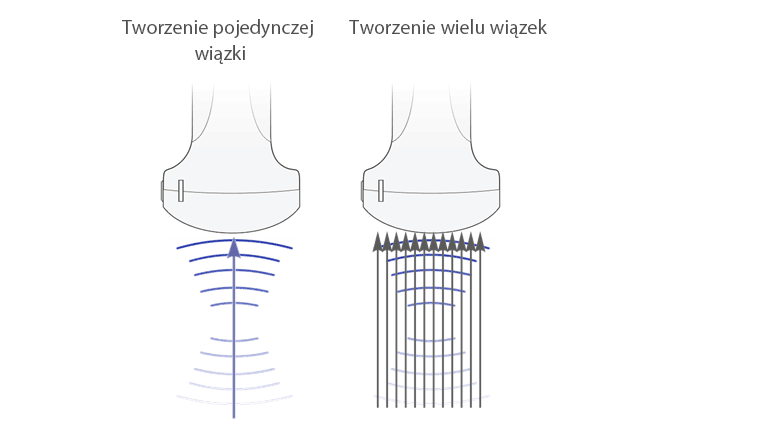

Multi-Beam Formation (Tworzenie wielu wi?zek)